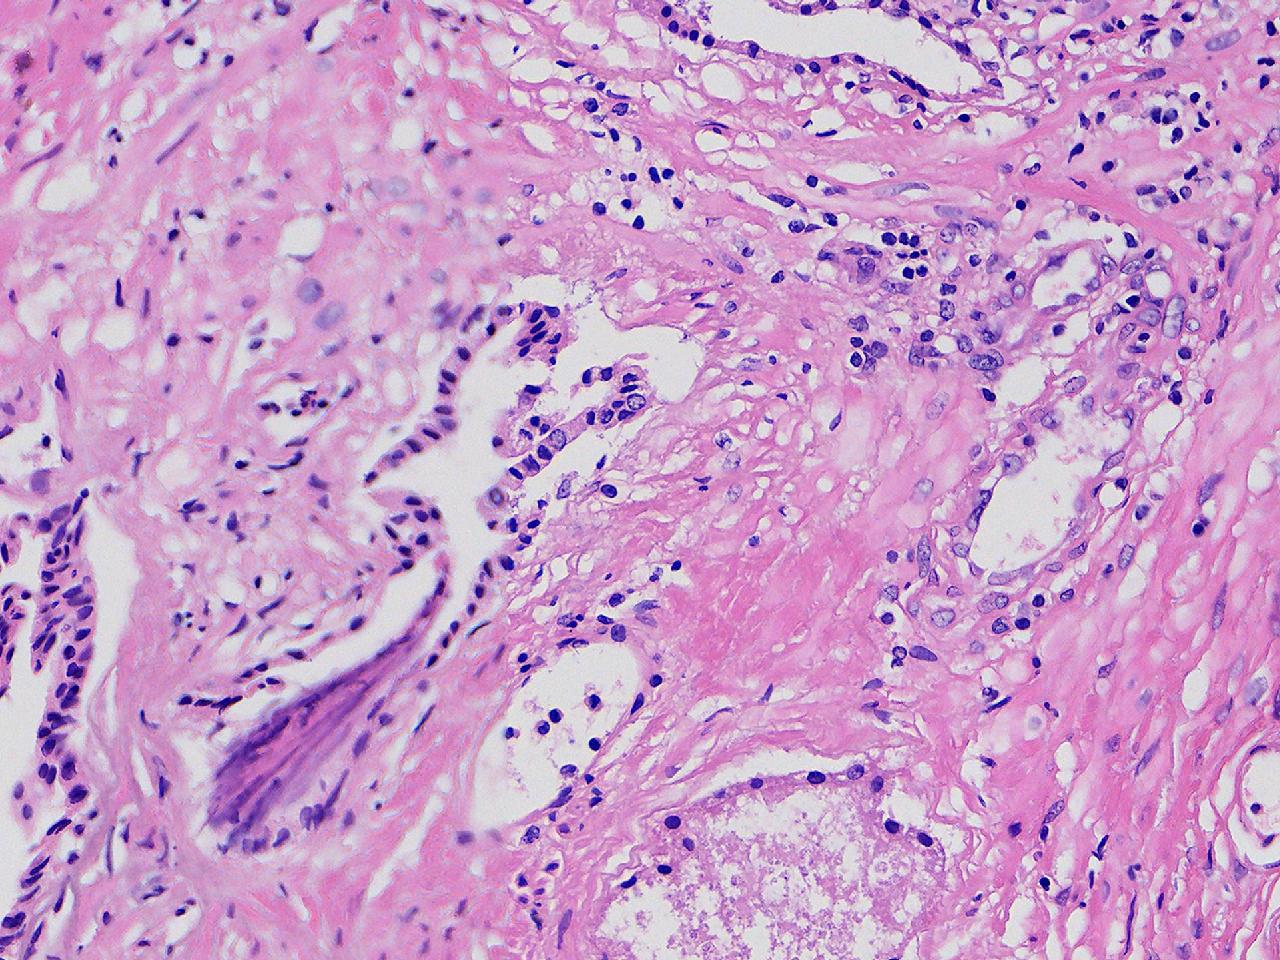

这些腺体有问题吗?

男,77岁,排尿困难2年,尿潴留3天。

标本名称

电切前列腺组织

条索状软组织多块,5X5X4厘米。